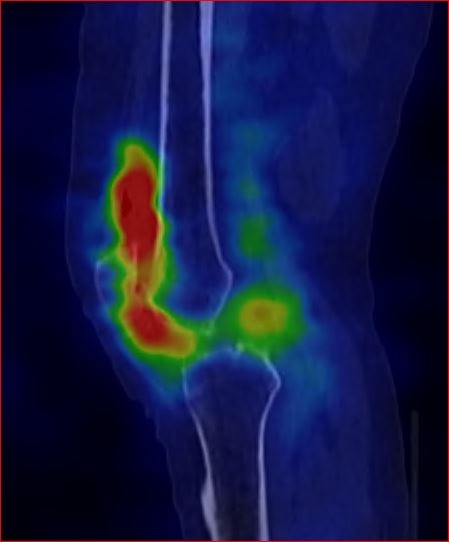

Pacientka přichází pro výrazné bolesti a recidivující výpotky levého

kolenního kloubu se scintigraficky potvrzenou výraznou synovialitis levého

kolenního kloubu (obr.1 a 2).

/ Obr.2.: SPECT/CT levého kolenního kloubu v časné fázi v sagitálním řezu - zvýšený krevní pool v oblasti synoviální membrány - scintigrafický nález odpovídá obrazu synovialitis.